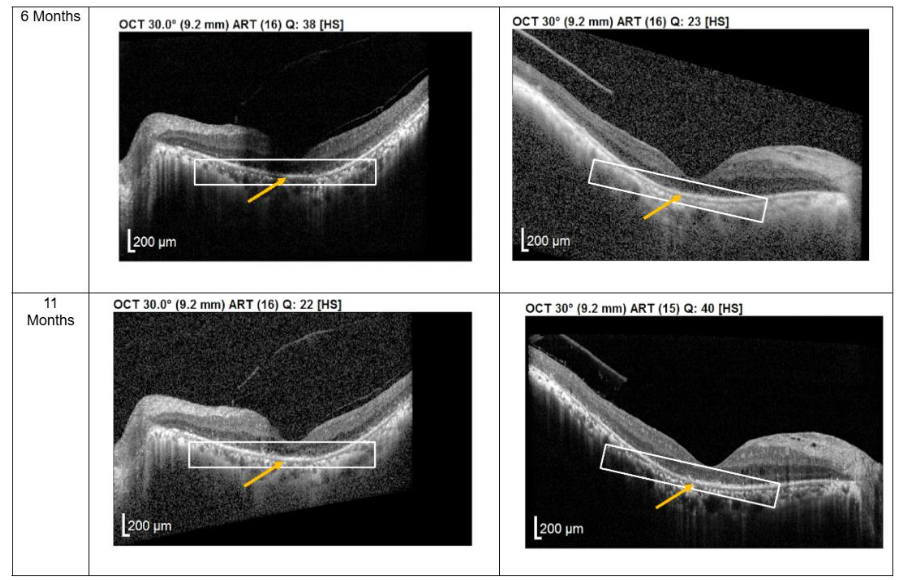

Patients 3 and 4

Patients 3 and 4 each received three subtenon MSC administrations at 4-6 weeks intervals, followed by follow-up visits every 3-4 months from December 2022 to November 2023. OCT imaging revealed a pronounced layer of photoreceptors accompanied by hyperreflective material at the interdigitation zone of the photoreceptor cells (PRCs), both at the macula and extramacular regions. These structural changes correlated with subjective reports from both patients of intermittent brighter vision, which persisted through the final follow-up.

Figure 3. Optical coherence tomography (OCT) images for both eyes of Patient 3 from pre-injection up to 1 year follow-up. Orange arrow demonstrates the presence of hyperreflective material at the interdigitation area of the photoreceptors at the macula and extramacular region. These were observed and maintained until the last follow-up examination.

At the 12-month follow-up, no adverse events were reported. As with the first two patients, no serious ophthalmic or systemic complications were observed, further supporting the safety profile of subtenon MSC administration.

Structural changes observed on optical coherence tomography (OCT) provide additional insight into the biological effects of treatment. All patients demonstrated persistent hyperreflective material localized at the interdigitation zone of the photoreceptors. Rather than representing fibrotic change, this OCT finding may reflect photoreceptor outer segment remodeling, improved mitochondrial activity, or enhanced metabolic integrity of surviving photoreceptors. Similar hyperreflective changes have been reported in studies evaluating MSC-mediated neuroprotection and are often associated with functional stabilization rather than disease progression. The stability of these OCT findings over extended follow-up in patients 1 and 2 suggests a sustained therapeutic effect rather than a transient inflammatory response.